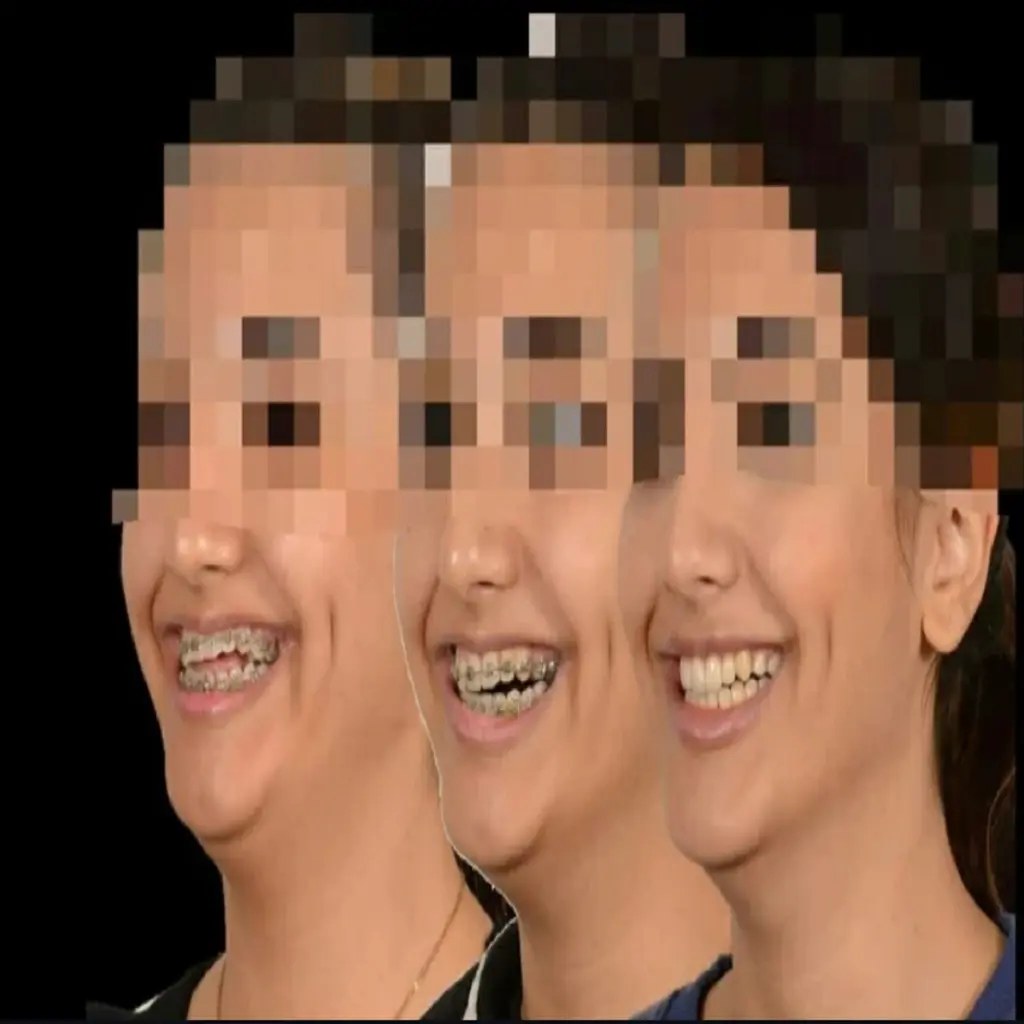

۳. دکتر فرزاد یحیی پور – تلفیق هنر و تخصص در لبخند

دکتر فرزاد یحیی پور یکی دیگر از پزشکان حاذق در لیست ما هستند که مطب ایشان در منطقه سعادت آباد واقع شده است. ایشان با نگاهی زیبایی شناسانه به درمان ارتودنسی می پردازند و هدفشان تنها صاف کردن دندان ها نیست، بلکه هماهنگی خط لبخند با اجزای صورت است.

ایشان دارای بورد تخصصی ارتودنسی بوده و عضو انجمن ارتودنتیست های ایران و اروپا هستند. استفاده از براکت های سرامیکی و دیمون (Damon) برای کاهش طول دوره درمان، از خدمات ویژه مطب ایشان است. محیط آرام مطب و برخورد حرفه ای پرسنل، به همراه نظم در نوبت دهی که کمترین معطلی را برای بیمار دارد، از نقاط قوت ایشان است.

🦷 نمونه درمان ارتودنسی دکتر فرزاد یحیی پور: